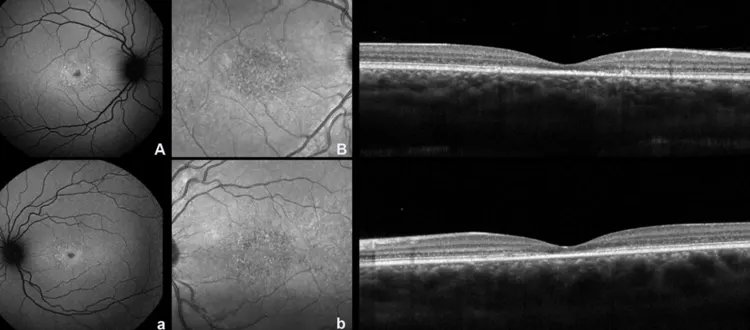

Retinitis pigmentosa (RP) is the collective term for a fixed of hereditary retinal problems that lead to the unconventional degradation of photoreceptor cells in the retina, which in turn reasons loss of vision and subsequently blindness. Mutations in several genes which are important for the shape and function of photoreceptor cells cause the situation. Night

Stargardt’s disease, also known as Stargardt macular dystrophy, is a genetic circumstance of the eyes that effects in progressive vision loss, typically beginning in the youth. The ABCA4 gene is frequently mutated to induce this kind of adolescent macular degeneration, that is generally discovered. Retinal pigment epithelium (RPE), unfavourable photoreceptor cells, and toxic byproduct accumulation